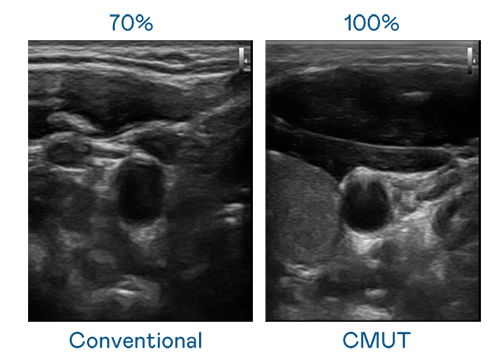

CMUT 技术是一种用电容式微机电元件来产生超音波讯号的技术。与传统 PZT 压电式技术相比,CMUT 频宽增加 30%,更宽频的超音波讯号让影像解析度大幅提升,是实现高影像品质医疗超音波扫描、促进精准医疗发展的关键技术。

超音波影像的解析度高低,首先取决于探头能发出的讯号频宽。凯发k8 CMUT 可提供高清晰的超音波讯号,提供高频宽、高灵敏度、影像纹理细节更高的超音波影像,协助医护人员缩短影像判读时间及利用精准的医疗影像进行诊断。